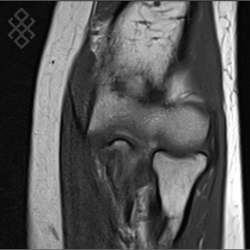

IRM du Coude

Vous entrez dans l'aimant, ouvert des 2 côtés, la tête la première et allongé sur le dos avec les bras le long du corps. Pour recueillir le signal et construire les images, vous aurez le coude dans une antenne. Étant donné que cet examen est bruyant, vous aurez à votre disposition des tampons auriculaires pour atténuer le bruit de la machine.